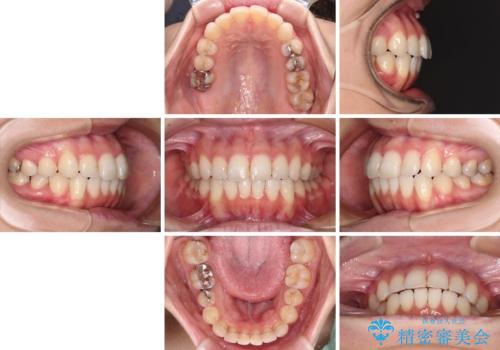

【モニター】前歯のデコボコをインビザラインできれいに整える

- 前歯のデコボコを気にして来院された患者様です。

主に下顎歯列全体の後方移動とIPR(歯と歯の間を削る)によってデコボコが解消するように設計し、インビザラインにより治療を行うこととしました。

舌突出癖がある方ですと、叢生が解消すると同時に前方に拡大されてしまいますが、ゴムかけをしっかりと行ってくださったこともあり、スッキリとした仕上がりとなりました。